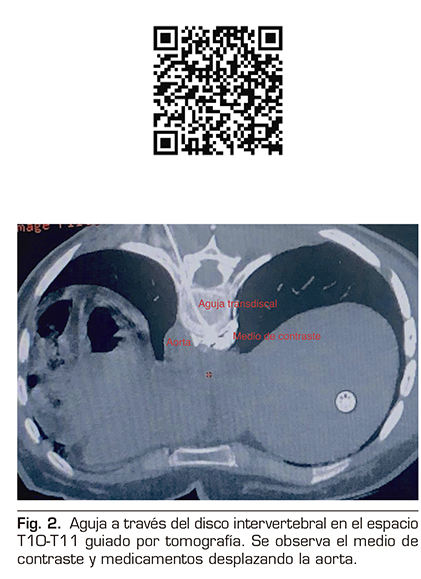

Se realizó un abordaje transdiscal de los nervios esplácnicos a nivel de T10-T11 guiado por tomografía.

Con la paciente en decúbito prono se identificó el espacio seleccionado, se infiltró lidocaína al 1 % a 5 cm de la línea media izquierda y se avanzó una aguja espinal número 22 progresivamente, realizando cortes topográficos hasta alcanzar el retromediastino. Se confirmó la punta de la aguja con 2 ml de medio de contraste iopromida 300 mg/ml (Ultravist®), y se procedió a inyectar bupivacaína 0,5 % más metilprednisolona 80 mg para un total de 10 ml (Figura 2).

Además, se debería tener siempre presente el manejo intervencionista del dolor cuando los fármacos no brindan analgesia efectiva o producen efectos adversos importantes, ya que constituye un escalón más de la escalera analgésica de la OMS, y se convierte en un importante recurso (16), como lo fue en este caso, donde se realizó un bloqueo de los nervios esplácnicos guiado por tomografía que ofreció gran resolución espacial y ubicación exacta de la punta de la aguja en la reconstrucción 3D. La vía transdiscal fue elegida por ser la técnica que mejor manejamos al ser alumnos directos de quien la ideó (2); teóricamente, por su acceso puede disminuir el riesgo de complicaciones como paraplejia, neumotórax y perforación hepática o renal, sobre todo en pacientes con anatomía modificada. Asimismo, al ser un bloqueo retrocrural nos ofrece una importante barrera anatómica vs. el bloqueo del plexo celiaco (17).